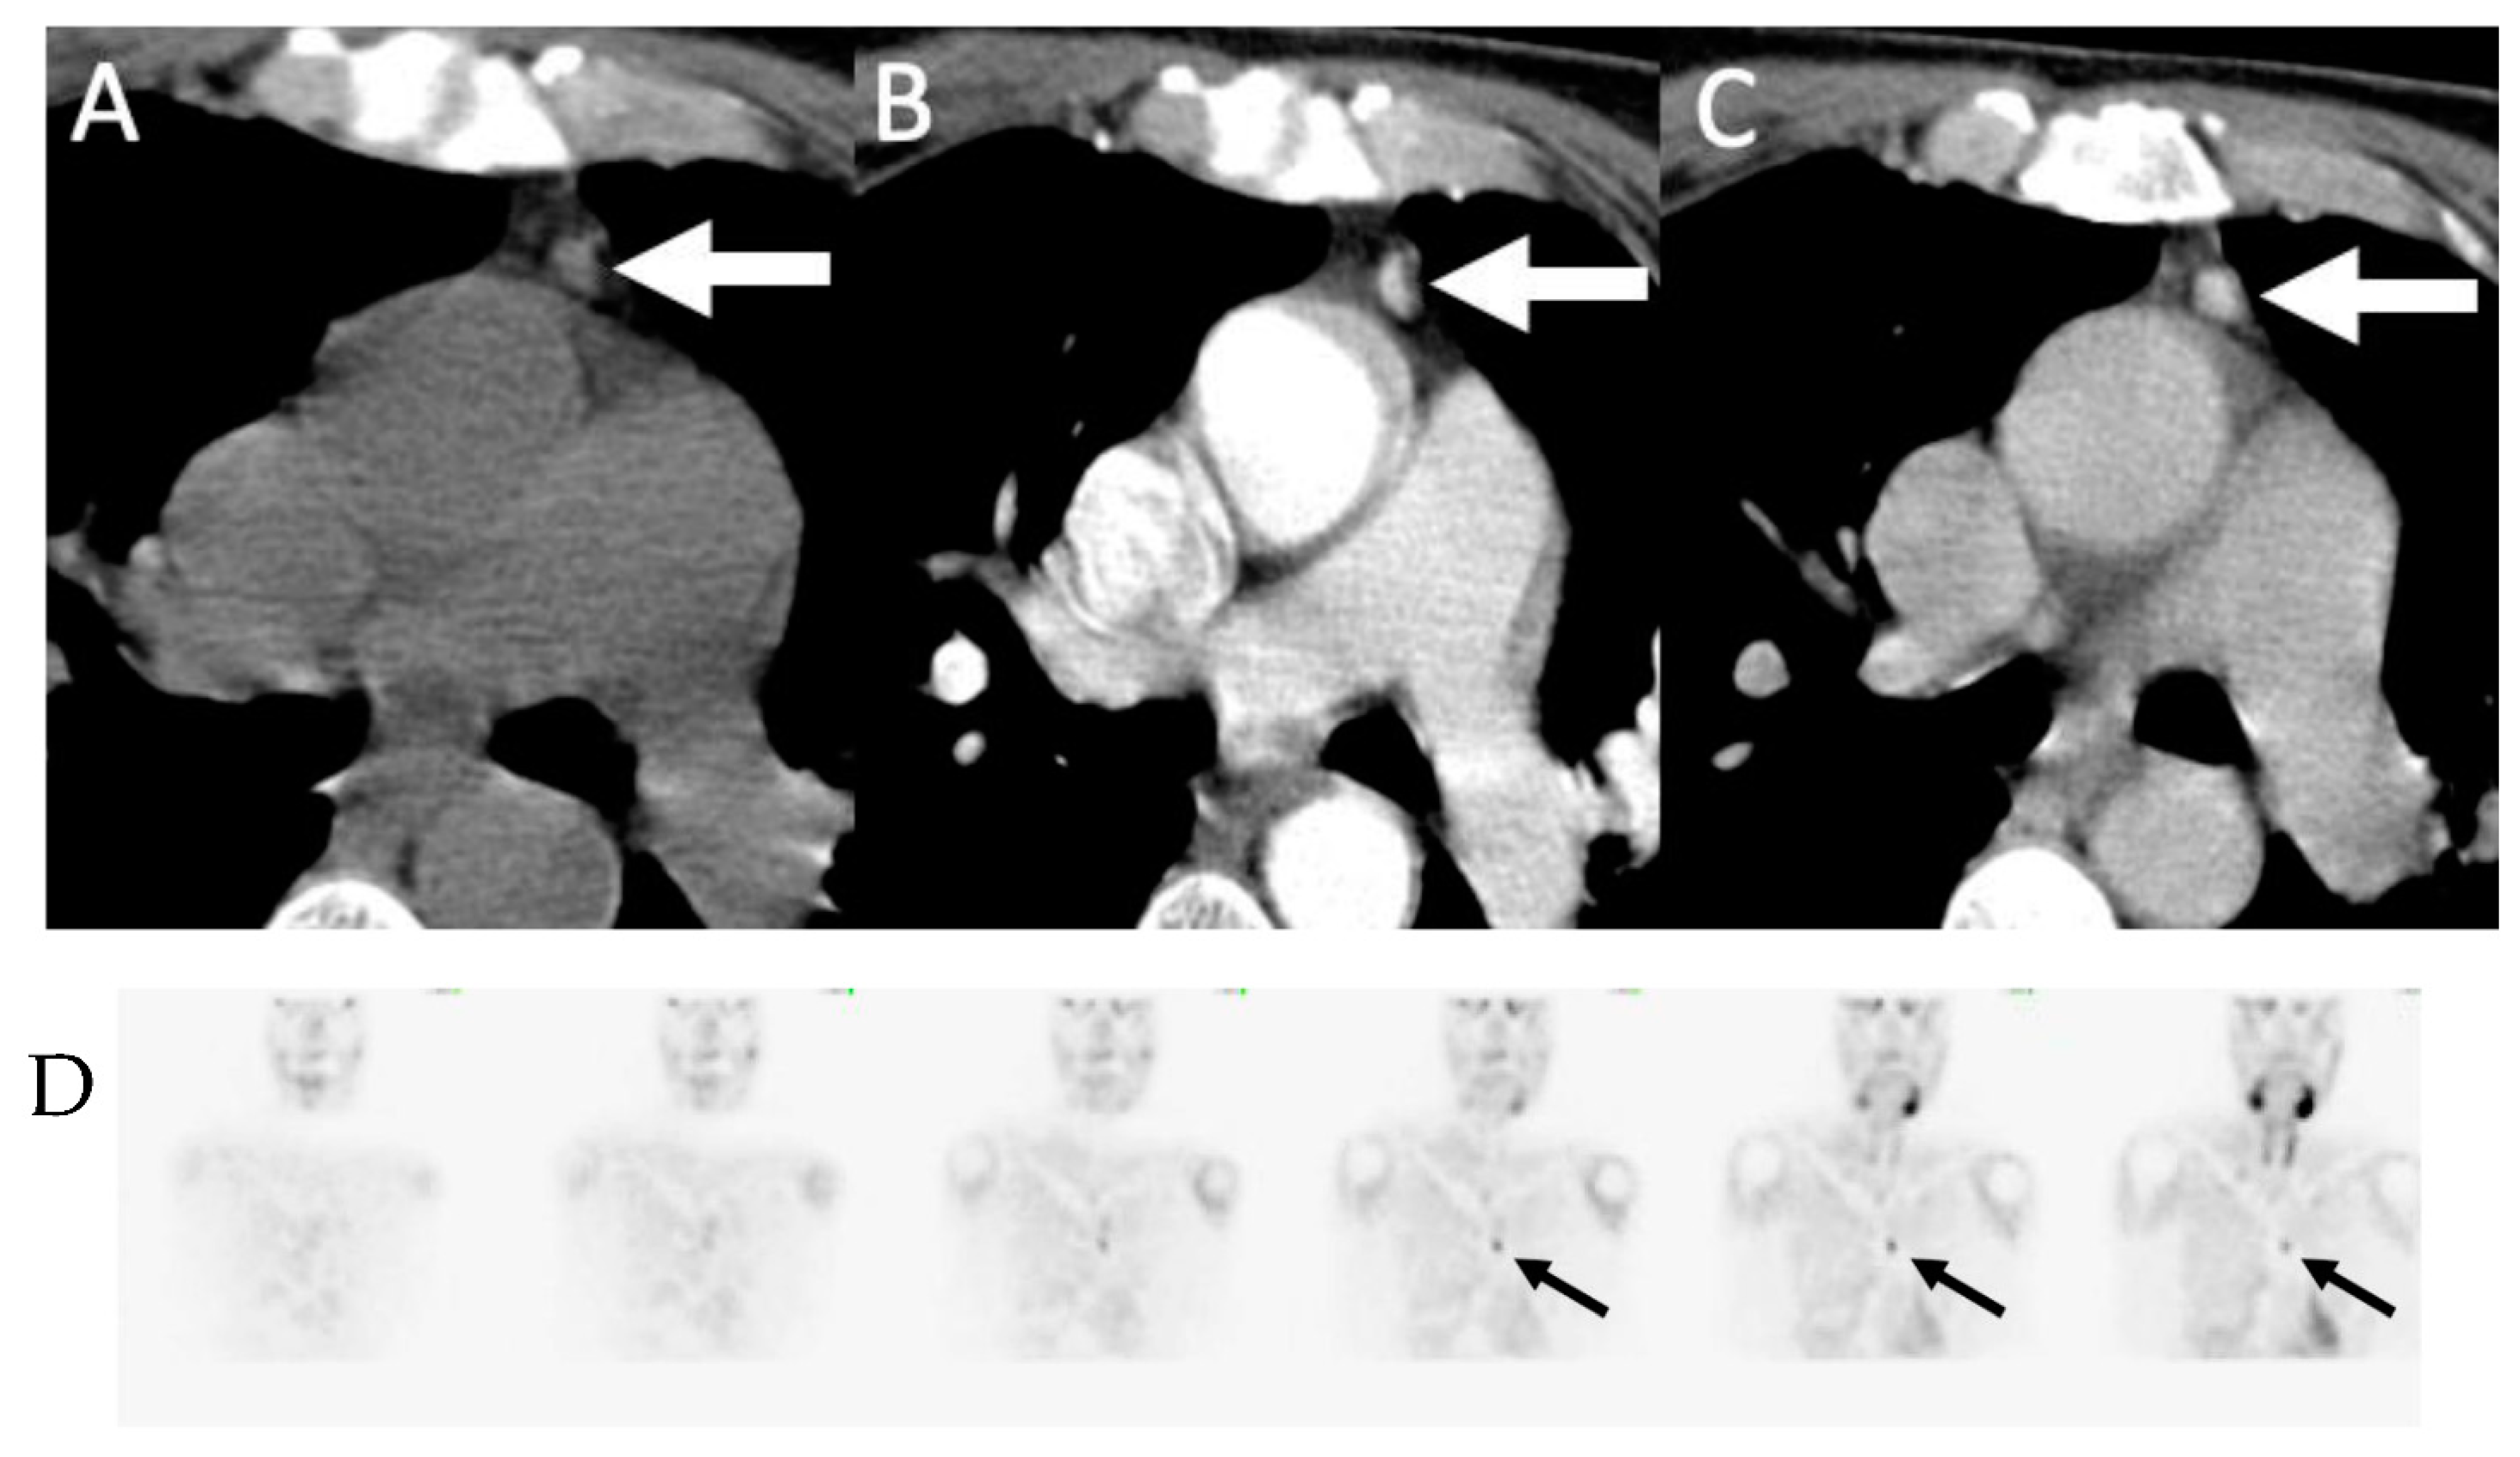

- Parvinian, A.; Martin-Macintosh, E.L.; Goenka, A.H.; Durski, J.M.; Mullan, B.P.; Kemp, B.J.; Johnson, G.B. 11C-Choline PET/CT for Detection and Localization of Parathyroid Adenomas. Am. J. Roentgenol. 2018, 210, 418–422. [Google Scholar] [CrossRef] [PubMed]

- Liu, Y.; Dang, Y.; Huo, L.; Hu, Y.; Wang, O.; Liu, H.; Chang, X.; Liu, Y.; Xing, X.; Li, F.; et al. Preoperative Localization of Adenomas in Primary Hyperparathyroidism: The Value of 11C-Choline PET/CT in Patients with Negative or Discordant Findings on Ultrasonography and 99mTc-Sestamibi SPECT/CT. J. Nucl. Med. 2019, 61, 584–589. [Google Scholar] [CrossRef]